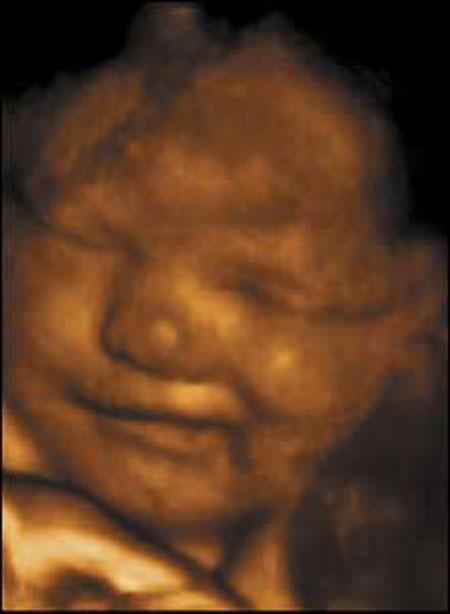

Ультразвуковые съёмки аборта на 12 неделе явно показывают: ребёнок чувствует боль, как любой из нас, и прекрасно понимает, что его хотят убить - он всеми силами старается отодвинуть от себя инструмент и широко раскрывает рот в безмолвном крике, когда у него отрывают сначала ноги, затем часть туловища…

Голову извлекают в последнюю очередь и лицо убитого ребёнка всегда искажено гримасой боли и ужаса. По этим кадрам видно, что практически нет разницы, убить ли 3-месячного ребёнка в утробе или отрезать руки -ноги -голову 5-летнему малышу. Без анестезии и в полном сознании.

- Фильм американского врача Бернарда Нэйтансона, названный «Безмолвный крик», показал всему миру, что такое аборт на сроке 11 недель беременности. Многие врачи и медсестры, посмотрев фильм, прекратили участвовать в абортах.

Это документальный фильм, и авторы рекомендуют соблюдать осторожность при его показе, поскольку некоторые кадры могут вызвать у человека психологический шок: безмолвный крик внутриутробного младенца, искаженное от боли лицо ребенка, погибающего на наших глазах...

Из закадрового текста к фильму: «Инструмент еще не коснулся ребенка, но он уже возбужден, его сердечные удары учащаются и достигают приблизительно 200 ударов в минуту. Вакуум-кюретка нащупывает ребенка, и он широко раскрывает рот в безмолвном крике».